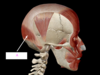

which of the following is attaches to the eyeball posterior to the eyeball equator?

superior rectus

inferior olbique

medial rectus

lateral rectus

superior oblique

what movement does this cause? [1]

which of the following is attaches to the eyeball posterior to the eyeball equator?

superior rectus

inferior olbique

medial rectus

lateral rectus

superior oblique

what movement does this cause? [1]

depression of eye